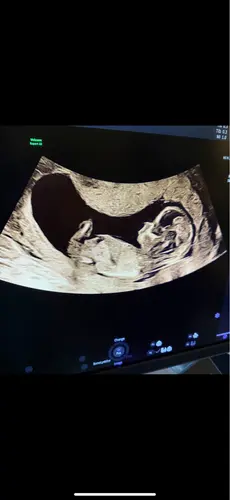

Wellicht dat ik hier tussen kom haha.. ziet iemand wat het is?😂

Duidelijk meisje!